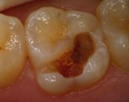

Ett stort hål